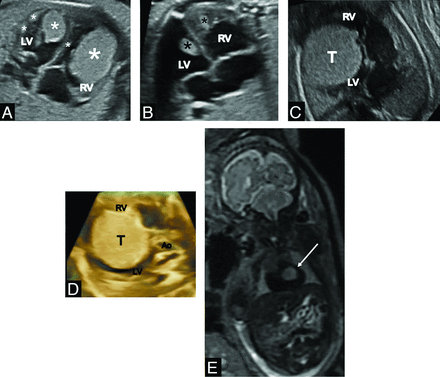

Cardiac rhabdomyomas are quite easy to detect during fetal echocardiography. They usually occur in the third trimester of pregnancy, so most of them cannot be seen during the US, which is performed around 20 weeks of gestation. The US appearance of rhabdomyomas is very characteristic (Fig 1A–D). They are histologically benign; however, they are a typical sign of TSC. It is important to check their location because sometimes they obstruct inflow or outflow of the heart. Although they occur very rarely, they are a life-threatening condition for neonates, so perinatal specialist care should be instituted.

Typical echocardiographic images of multiple cardiac tumors (rhabdomyomas) in 3 different fetuses (fetus 1, 38 GWs (A); fetus 2 (B), 35 GWs; fetus 3 (C and D). A and B, Tumors are located in both ventricles and attached to the ventricular walls and interventricular septum and do not disturb blood flow. C and D, A huge cardiac tumor located in the RV, compressing the LV, and disturbing blood flow through both ventricles (C, 2D view; D, 3D view). E, MR imaging at 30 GWs. SSFSE/T2-weighted image, coronal plane: hypointense cardiac tumor (arrow) against the background of the “black hole” of a heart. RV, right ventricle; LV, left ventricle; Ao, aorta; T and/or * tumor.

Cardiac rhabdomyomas have a quite typical appearance on US. They are usually firmly attached to the heart muscle, interventricular or free ventricular walls, rarely in the atria. They are always oval and have various sizes, from a few millimeters to the huge tumor that involves most of the cardiac cavity. Most commonly, their diameter is a few millimeters, and they do not disturb blood inflow or outflow. They look slightly more hyperechogenic than the heart muscle.

On MR imaging, cardiac rhabdomyomas are uniformly hyperintense on SSFSE/T2-weighted images against the background of a dark heart that is called a “black hole” (Fig 1E). Being the most common cardiac tumors in the prenatal period, often multiple, they usually do not cause diagnostic uncertainty.